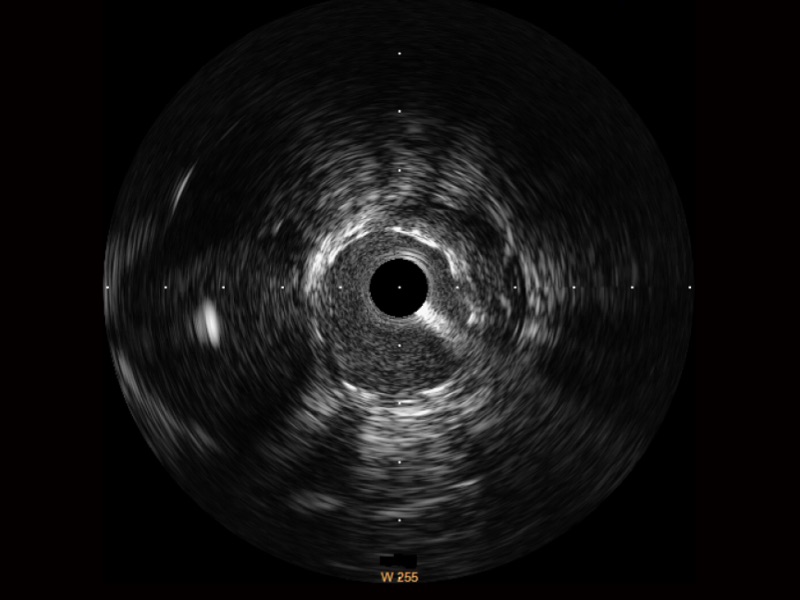

新葡的京集团8814检测站宽频IVUS图像

对比传统IVUS导管成像,新葡的京集团8814检测站宽频IVUS图像的近场支架梁显影更细腻,远场中膜外血管仍清晰可辨,兼顾远中近,兼顾分辨力与穿透深度